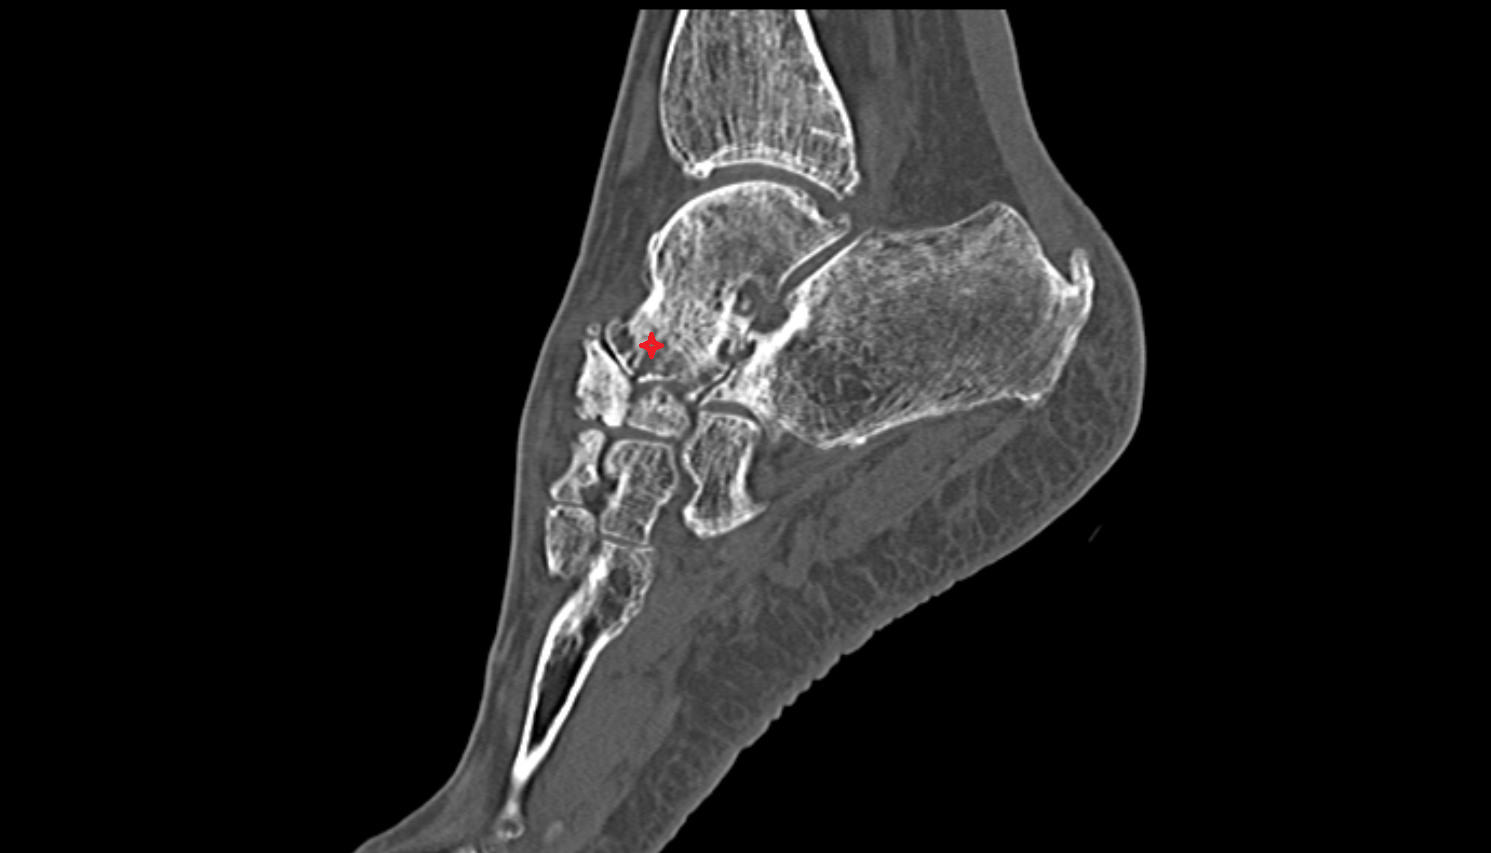

- Talus

- Head of talus

- Body of talus

- Neck of talus

- Calcaneus

- Ankle joint

- Talocalcaneal joint